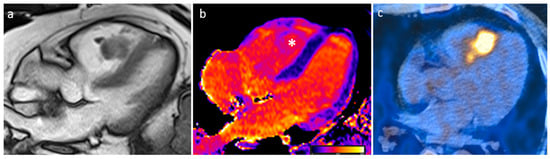

| Thrombus | Adulthood | LA, LAA (AF) LV (MI) | Asymptomatic, embolic events | Non-enhancing Intracardiac lesion | Acute: Low echodensity, rounded with smooth contours Chronic: High echodensity, linear or crescentic lesions along the endocardial surface | Low attenuation, no contrast enhancement, chronic thrombus may be calcified Usefulness of delayed CT imaging, as in the LAA stasis of blood can simulate a thrombus on early arterial images | Acute: hyper T1w and T2w Subacute: hyper T1w and hypo T2w Chronic: low T1w and T2w No enhancement. |

| Myxoma | Adulthood. Carney complex. | LA | Usually, asymptomatic. Rarely, intracardiac obstruction, embolic events and constitutional symptoms | Mobile mass arising from the IAS | Globular or spherical, with a friable surface and heterogeneous internal echogenicity | Heterogeneous, low attenuation, may be calcified | Isointense T1w, High T2w, heterogeneous LGE |